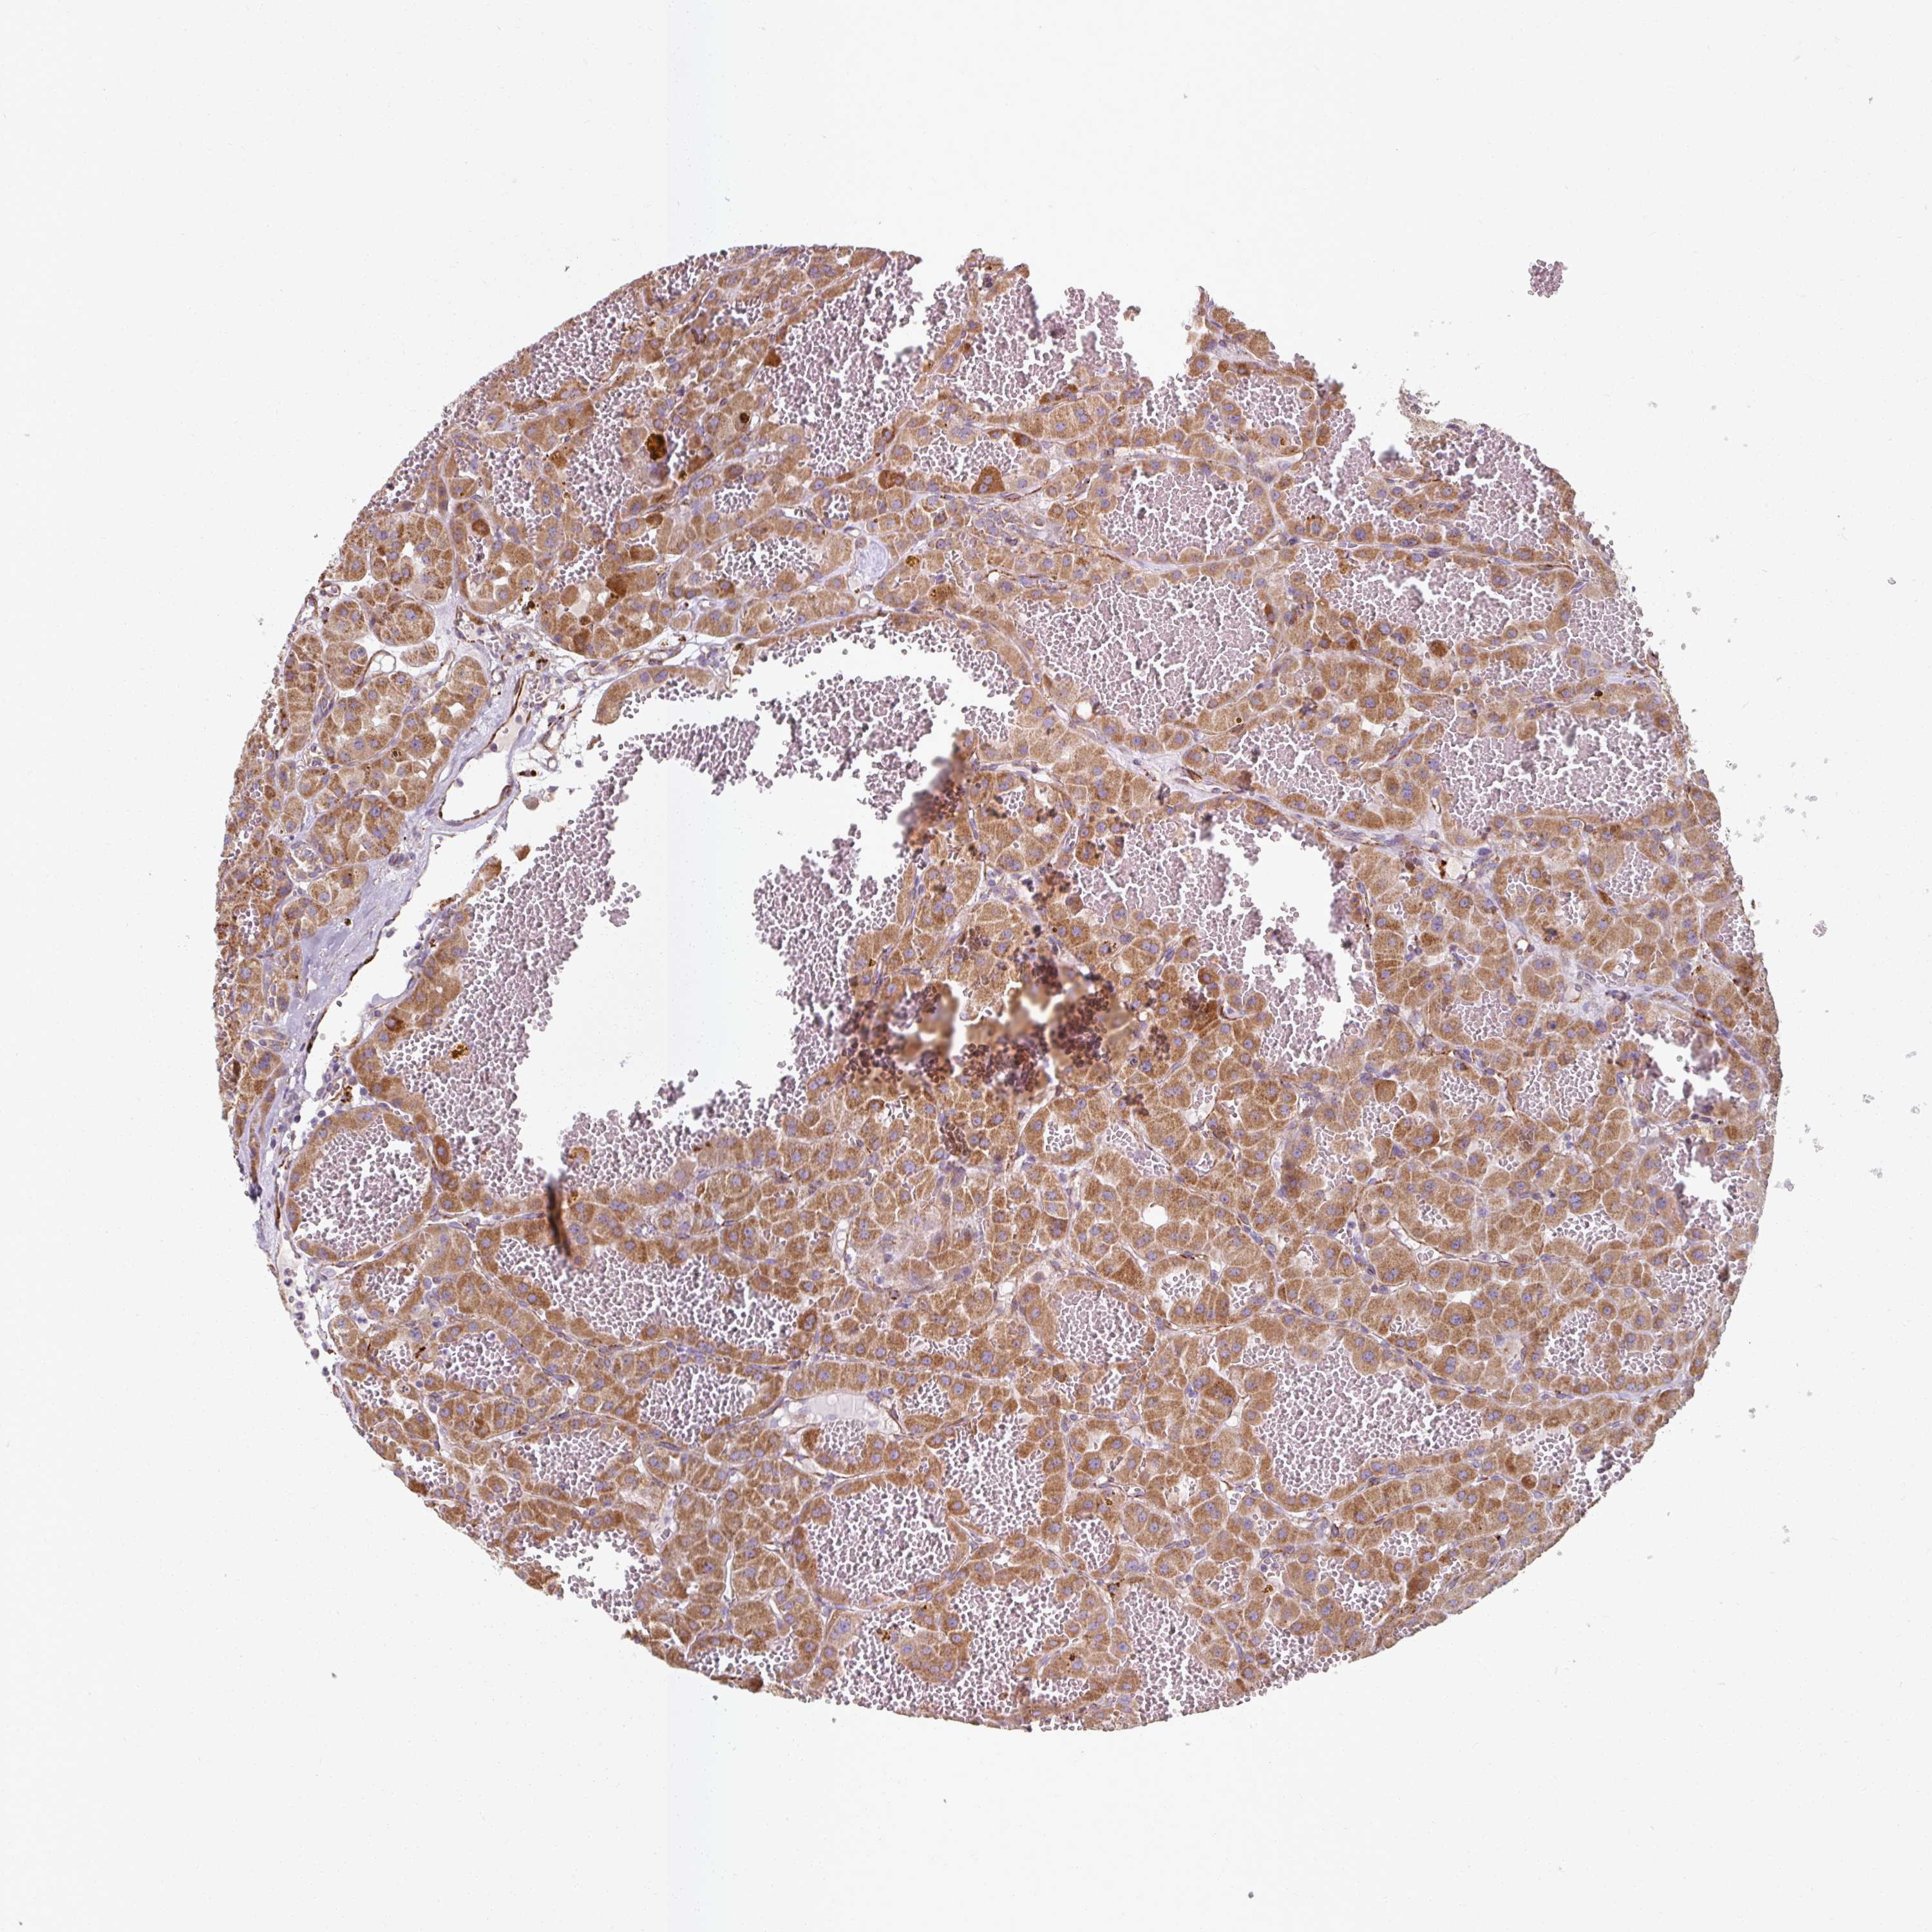

MRPS5

CANCER RENAL CANCER Show tissue menu